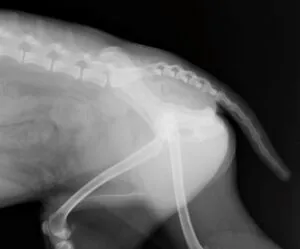

何度も再脱臼してしまう場合には、整形外科の専門病院にて外科的固定を行うこともあります。

写真は両側の股関節脱臼をして整形外科の専門病院にて外科的整復を行った別症例。